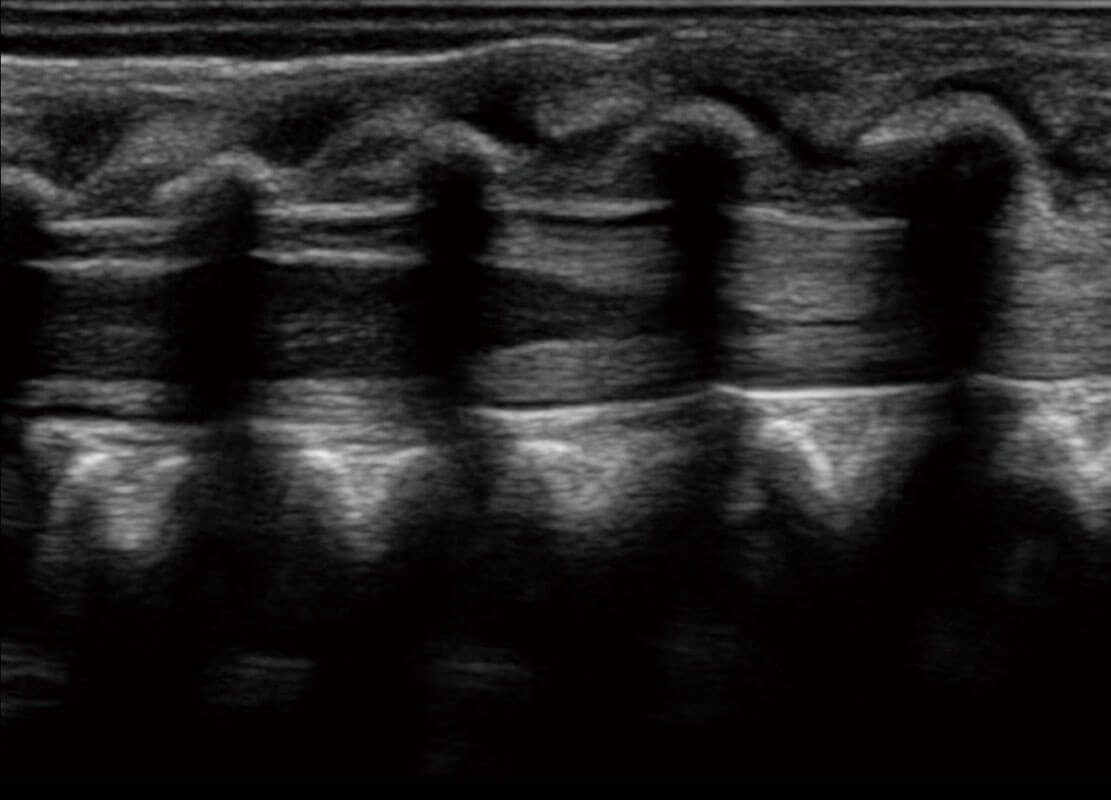

四腔切面

四腔心血流

右室双出口

胎心容积成像